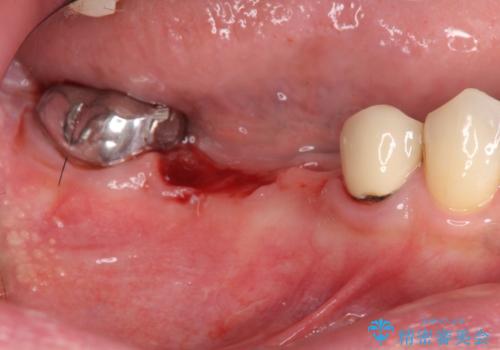

設計に無理のある長期的に良好な状態が保てるとは思えないブリッジを除去し、インプラントを用いた補綴計画を立てます。

- 外科手術のため、術後に痛みや腫れ、違和感を伴います

- メンテナンスを怠ったり喫煙により、お口の中に大きな悪影響を及ぼすインプラント周囲炎等にかかる可能性があります